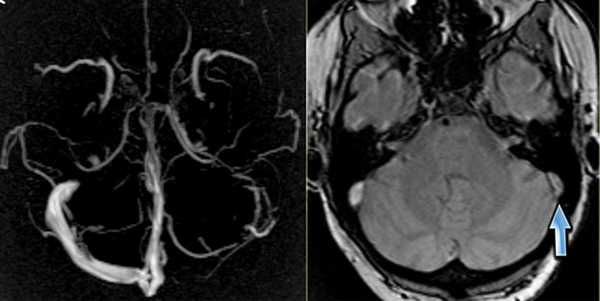

Тромбоз правого поперечного синуса - гипоинтенсивные участки по Т2 (внутриклеточный дезоксигемоглобин).

Для подтверждения тромбоза венозного синуса и определения точной локализации и протяженности тромба необходимо проведение МР-венографии.

МР-венография - отсутствие визуализации кровотока в правом поперечном синусе и яремной вене.